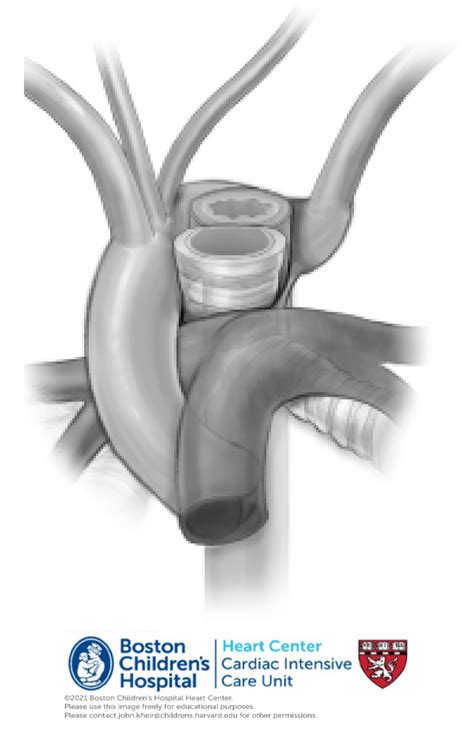

Surgical intervention is rarely required for an aberrant right subclavian artery unless the patient is experiencing severe, life-altering symptoms or if the vessel shows signs of an aneurysm. An aneurysm of the aberrant right subclavian artery—also known as a Kommerell's diverticulum—is a localized dilation at the origin of the artery that can increase the risk of rupture or severe compression.

When surgery is necessary, the goal is to relieve the compression of the esophagus or trachea. Modern techniques often involve a hybrid approach, which combines endovascular techniques (using stents or coils) with traditional thoracic surgery. This allows surgeons to safely bypass or reconstruct the vessel while minimizing the trauma to the patient's chest wall.